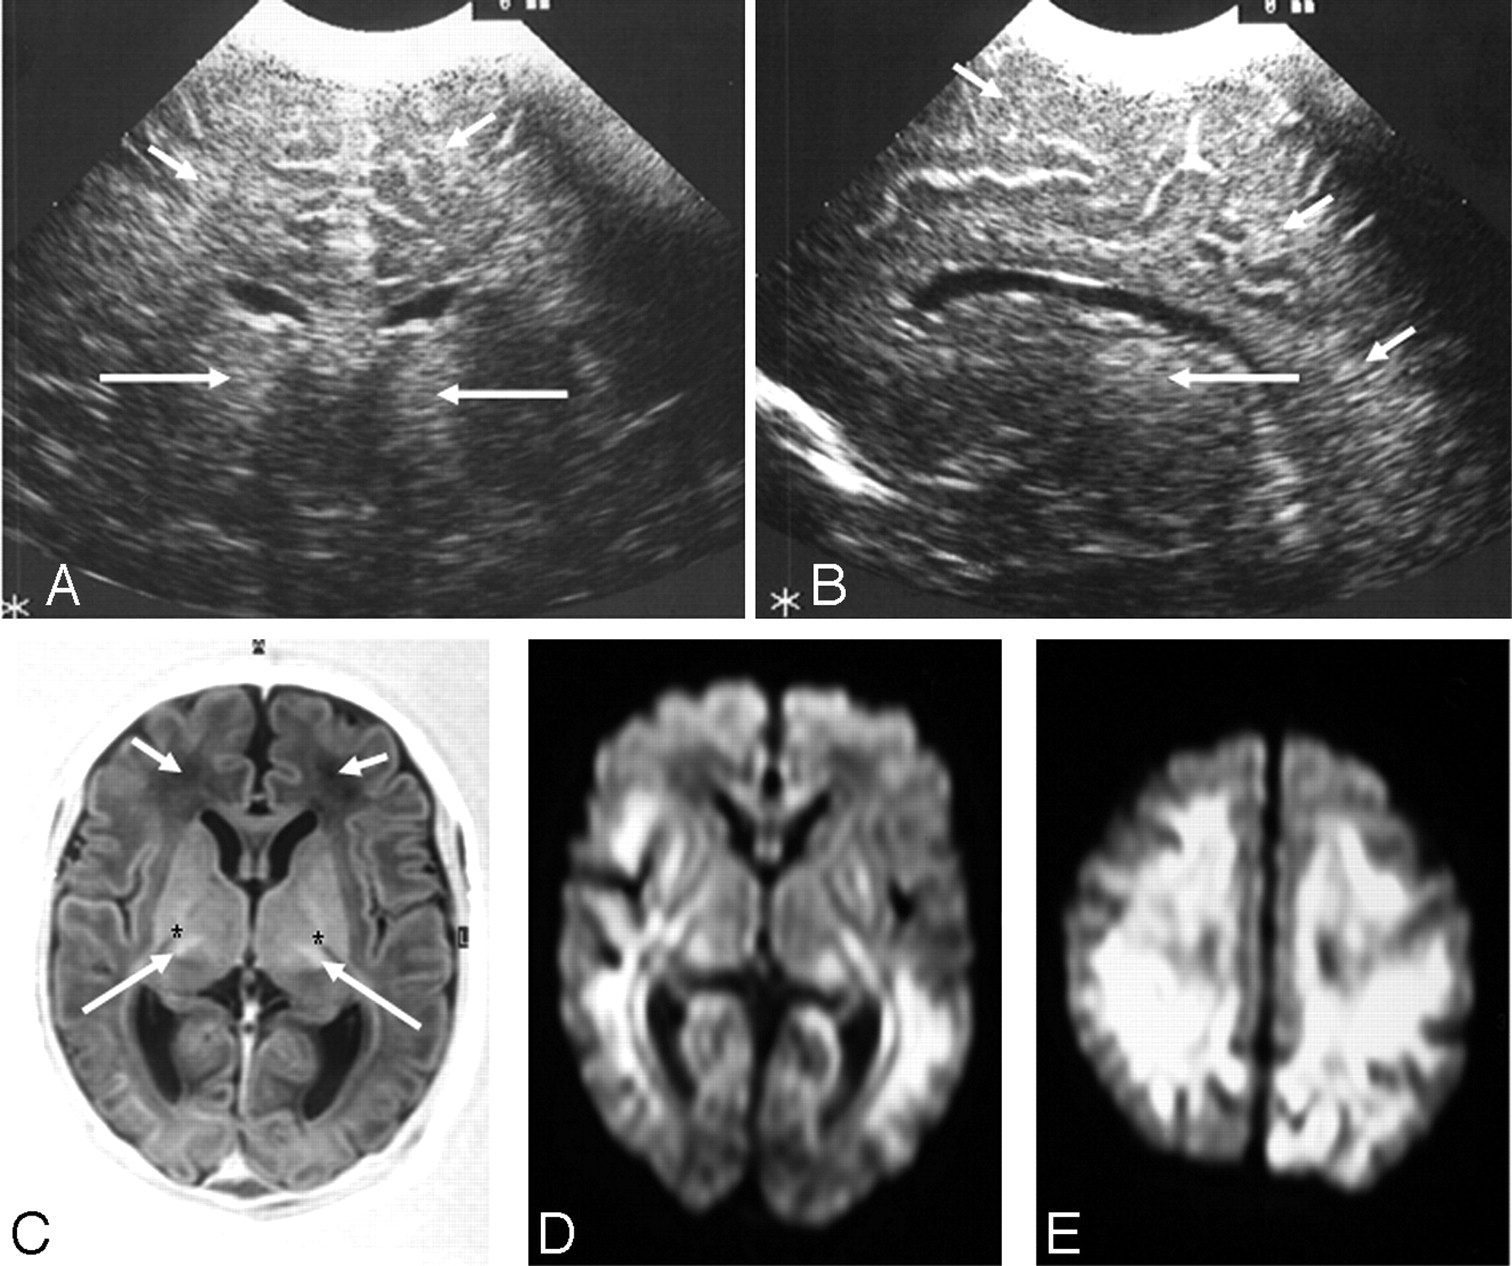

در سونوگرافی مغز با استفاده از یک پروب امواج صوتی وارد مغز می شود و تصاویر سیاه_سفید به وجود می آید که ساختار داخلی مغز و مایعی داخل بطن ها را نشان می دهد.

سونوگرافی سر در اغلب موارد برای کودکان کمتر از 6 ماه استفاده میشود. در کودکان بزرگ تر و بزرگسالان, استخوان جمجمه که به طور کامل تشکیل شده, امواج صوتی را مسدود می کند اما نوزادان به دلیل اینکه ملاج دارند، استخوان دو طرف جمجمه در وسط به طور کامل هنوز بهم متصل نشده و فضای خالی دارد و این فضای خالی به امواج صوتی اجازه عبور و انجام سونوگرافی را می دهد. پس سونوگرافی مغز یکی از انواع سونوگرافی نوزادان محسوب می شود.

- خونریزی در مغز ( IVH)

- آسیب به بافت های اطراف بطن های مغز (PVL)

- تجمع زیاد مایع در مغز یا بطن ها (هیدروسفالی)